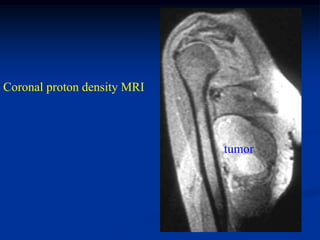

CLASSIC     Case #275               CT scan

59 year male with spindle cell lipoma thigh

Spindle Cell Lipoma The spindle cell lipoma is seen more commonly in men between the ages of 45 and 65 years and is typically located in the posterior neck or shoulder area. MRI imaging demonstrates the high signal features of a lipoma on the T-1 weighted image but with areas of lower signal streaking seen throughout the high signal areas where the fibrous tissue is located. Histologically, the spindle cell lipoma looks like any other lipoma except for the presence of benign- appearing fibrous tissue with occasional areas of gelatinous break- down in the fibrous tissue. The treatment for this variant is a marginal resection and carries a minimal chance for local recurrence.

CLASSIC Case #275 CT scan 59 year male with spindle cell lipoma thigh